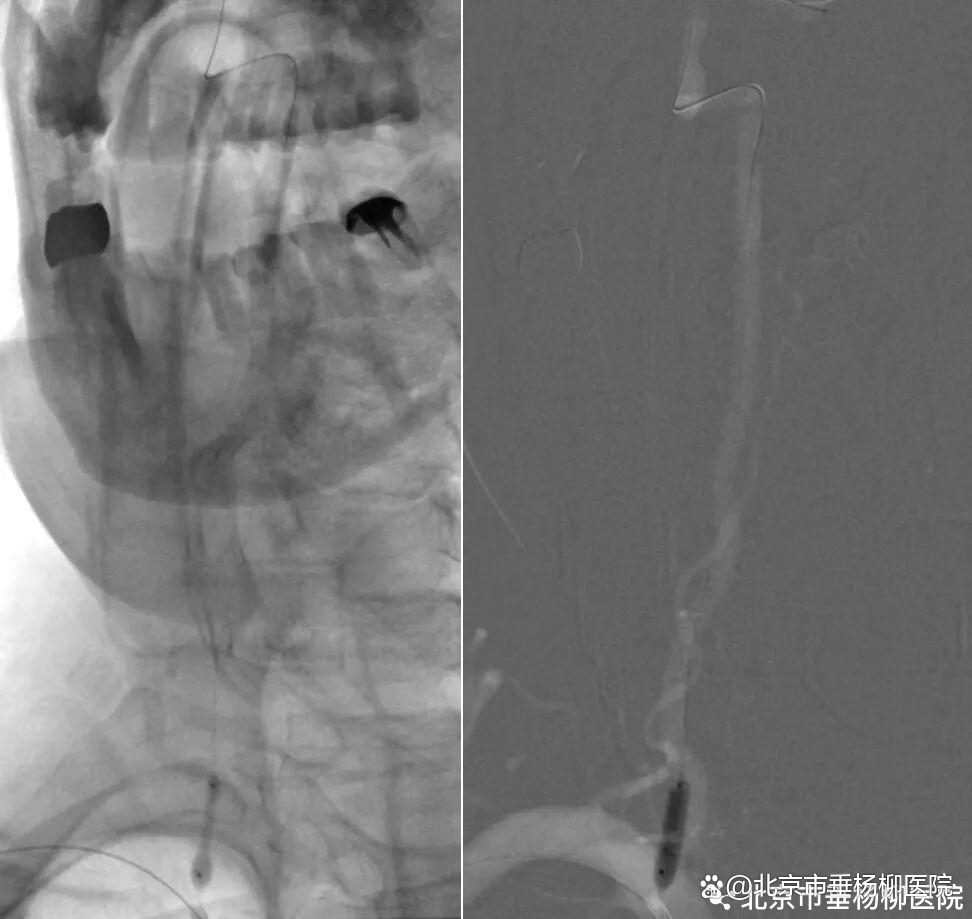

第一步,通路建立与保护。经股动脉穿刺建立通路。考虑到狭窄程度重,导引导管难以通过椎动脉开口,强行通过易导致斑块脱落,甚至损伤血管内膜致夹层。刘磊副主任医师应用小球囊穿梭技术顺利引导导引导管通过椎动脉起始狭窄处,到达指定位置。

第三步,解除狭窄,恢复血流。选择合适尺寸的球囊扩张式支架,精准释放于右侧椎动脉起始部狭窄段。